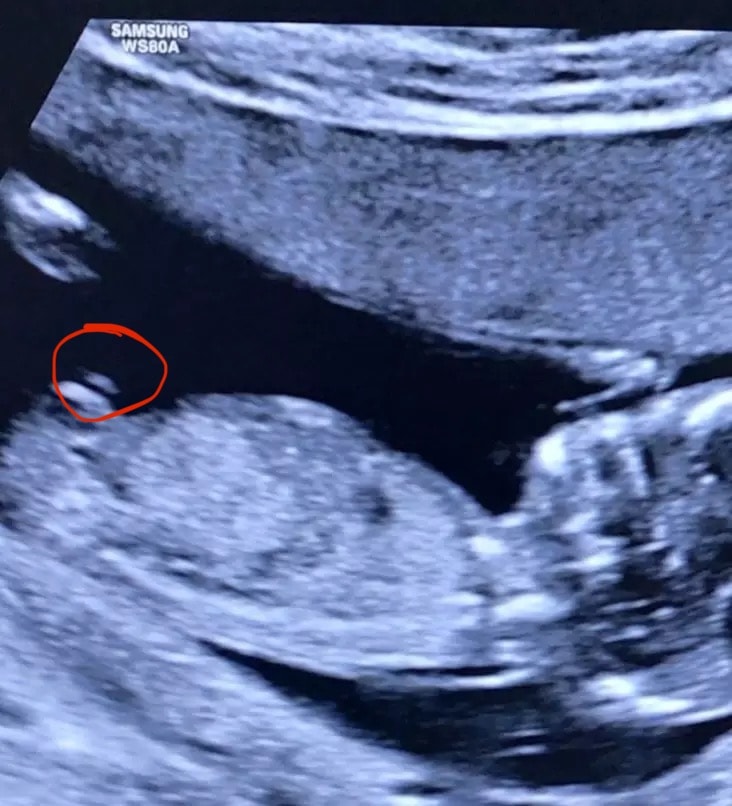

Пол малышаНу и я туда же)) через неделю второй скрининг,надеюсь скажут, читала,что как-то определяют по бугорку) фото со скрининга в 14 недель

Полина , вот я тоже думала,что это нога))фоткала с экрана,там стопкадры были,вот такое есть ещё